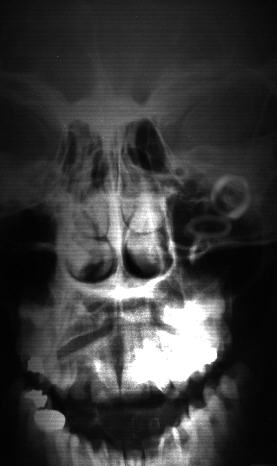

Above:  A computer-enhanced view of the implants.

Below:  The original XRAY as sent by Ed Kats.